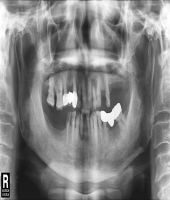

| ● 진료과목 : [임플란트] 틀니 사용중, 임플란트로 교체하기

| ● 내용 : 하악틀니 사용 중 불편감으로 임플란트로 교체한 예 |